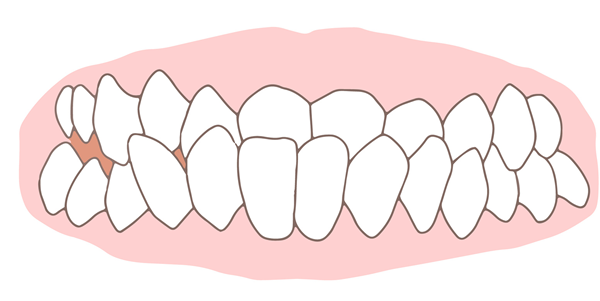

受け口

下の歯が前に出ているため、噛み合わせが逆になっている状態です。このため顎の動きが制約され、将来的に顎関節症になるリスクがあります。